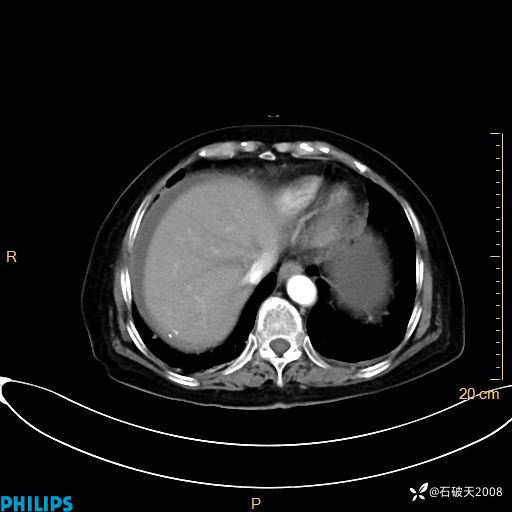

平扫